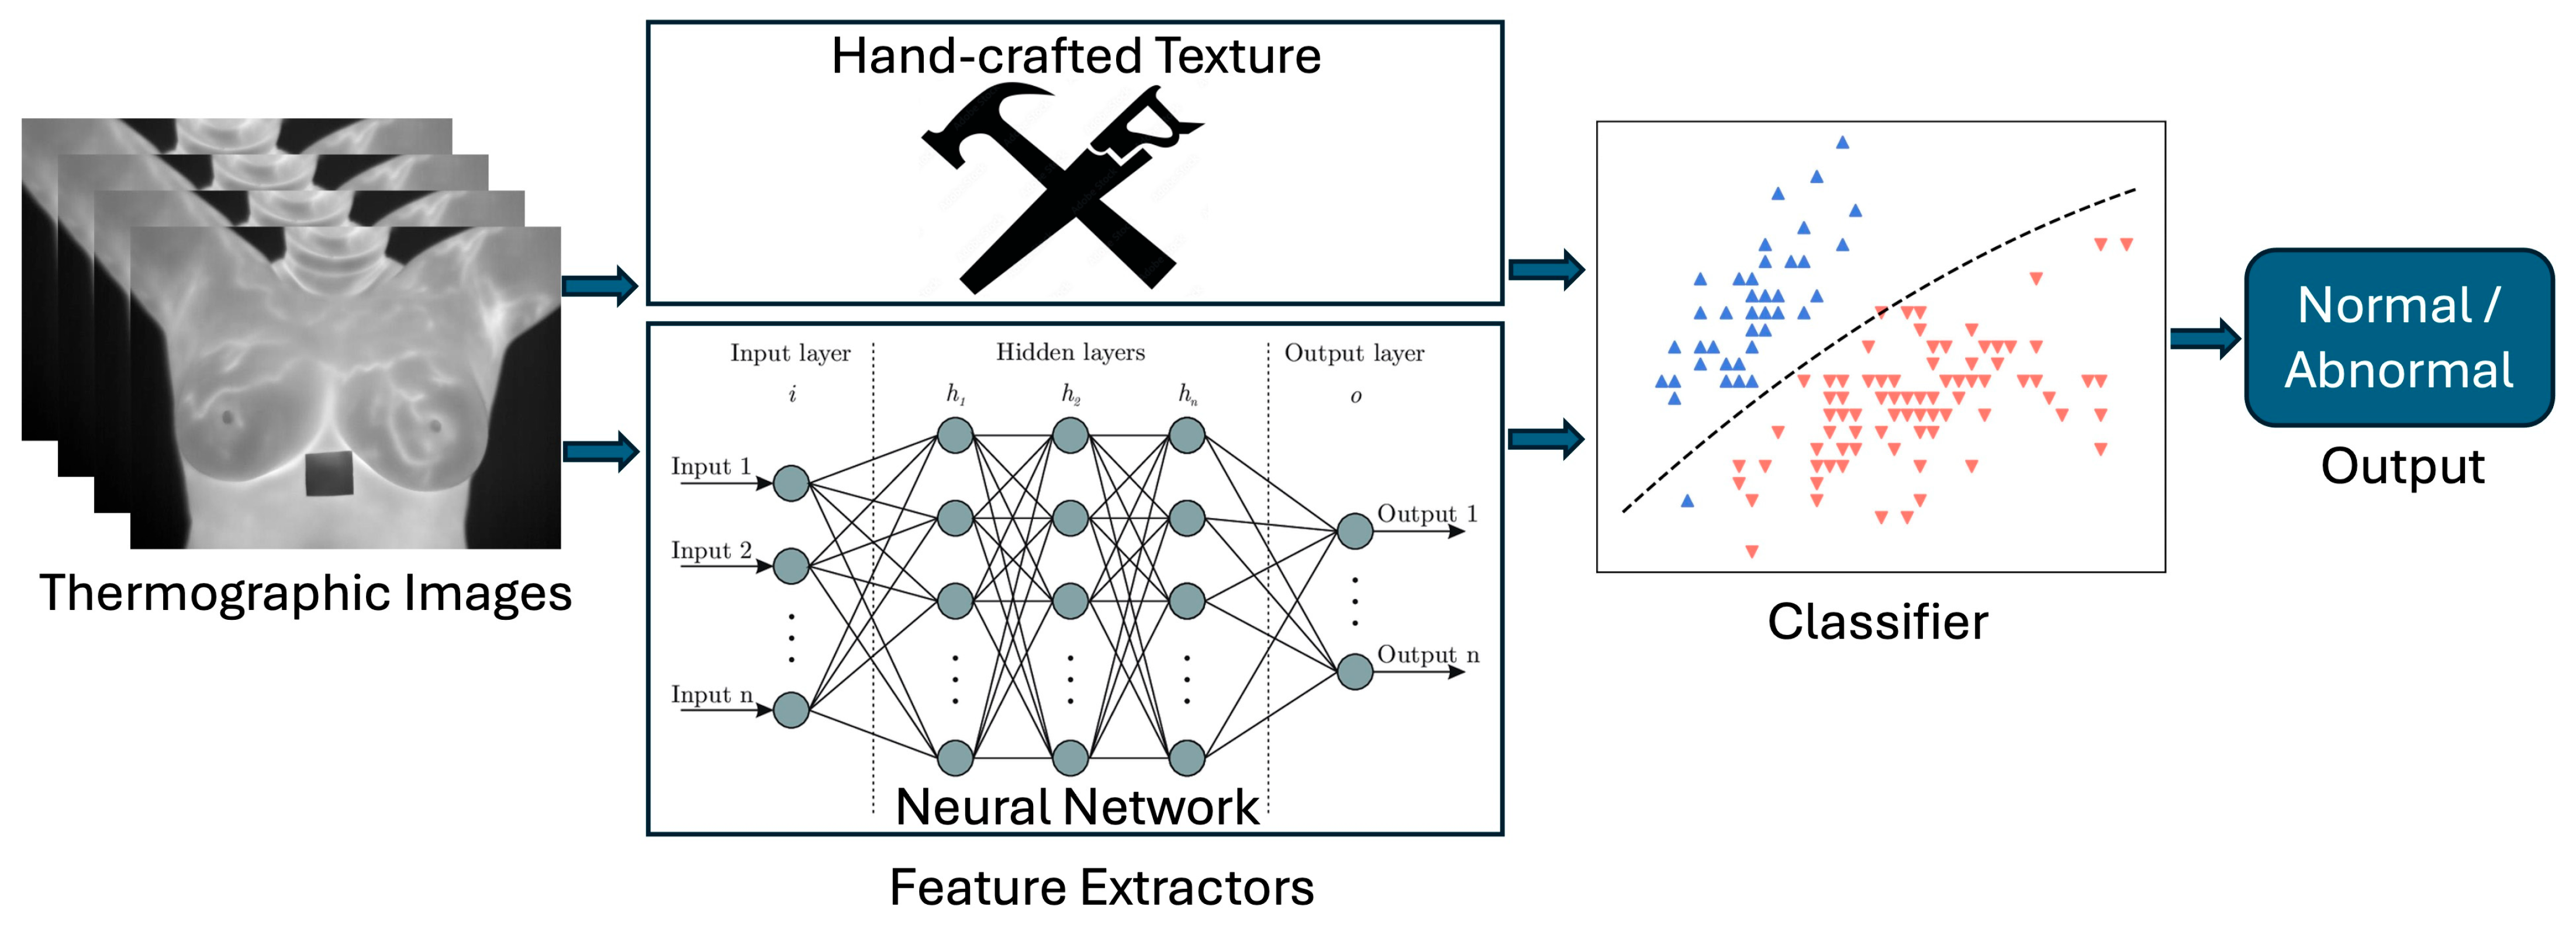

- A comprehensive review of recent advancements in texture analysis techniques and machine learning approaches specifically applied to breast cancer detection using infrared thermography, filling a gap in previous reviews that did not adequately emphasize texture analysis, and showing that this approach achieves top performance.

- A systematic analysis of the complete infrared thermography processing pipeline, including image preprocessing techniques, feature extraction methods, feature reduction techniques, classification approaches, and performance assessment metrics used in thermographic breast cancer detection, rather than focusing on isolated components of the workflow.

3.3. Feature Extraction